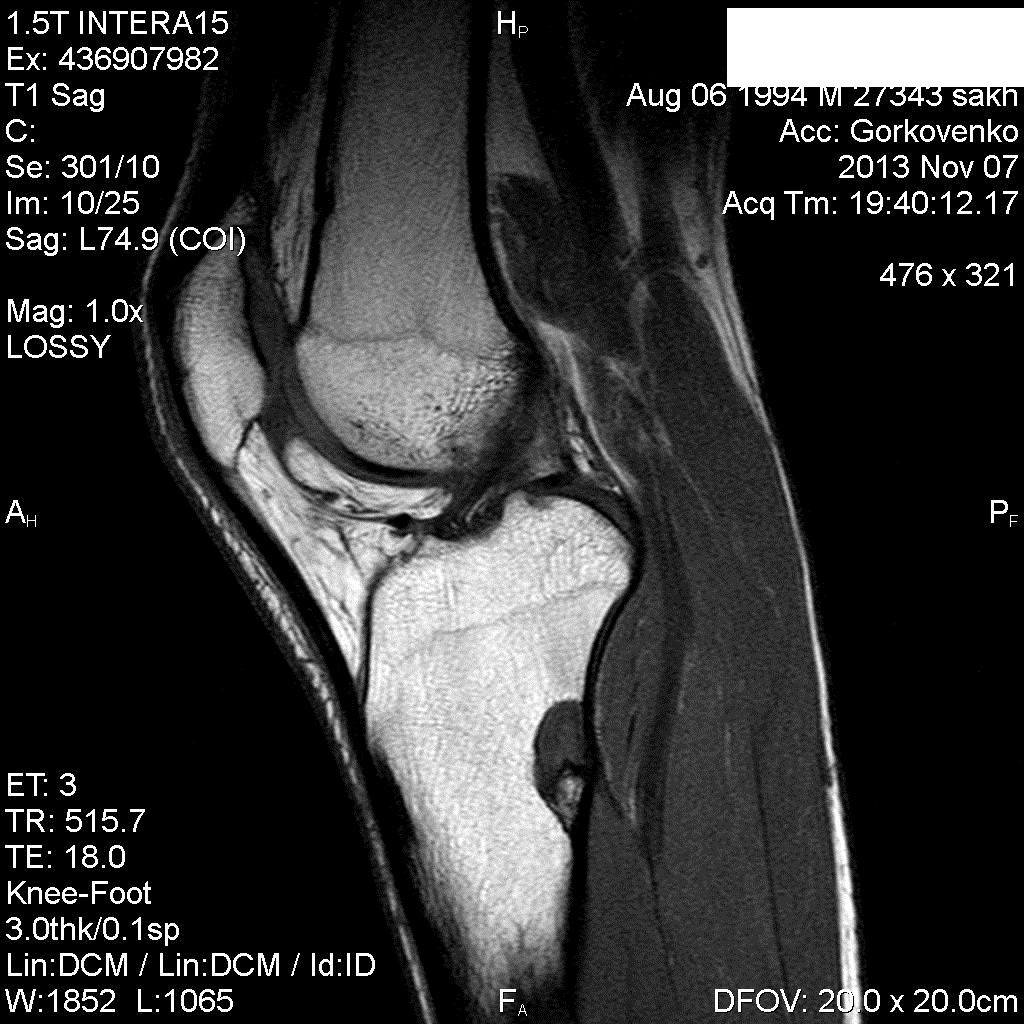

Образование верхней трети большеберцовой кости с признаками экспансивного роста, но кортикальный слой нарушен.По рентгенограммам заподозрила бы неоссифицирующую фиброму, но сигнальные характеристики смутили .Не может быть такая костная киста? Согласна, что кортикал не истончен, но вдруг?Еще рядом , ниже, мелкие тенюшки подозрительные..

я все же выскажусь в пользу NOF...

По-моему тоже за NOF больше данных, но я бы писал дифряд. А можно на снимок взглянуть, очень интересно?

nnemo, мне показалось в одном месте , что кортикал как бы клином сходится, то есть, истончение есть.

Я тоже больше склоняюсь к неоссифицирующей фиброме.Там еще ниже есть помельче подобная штука.Они бывают множественными?